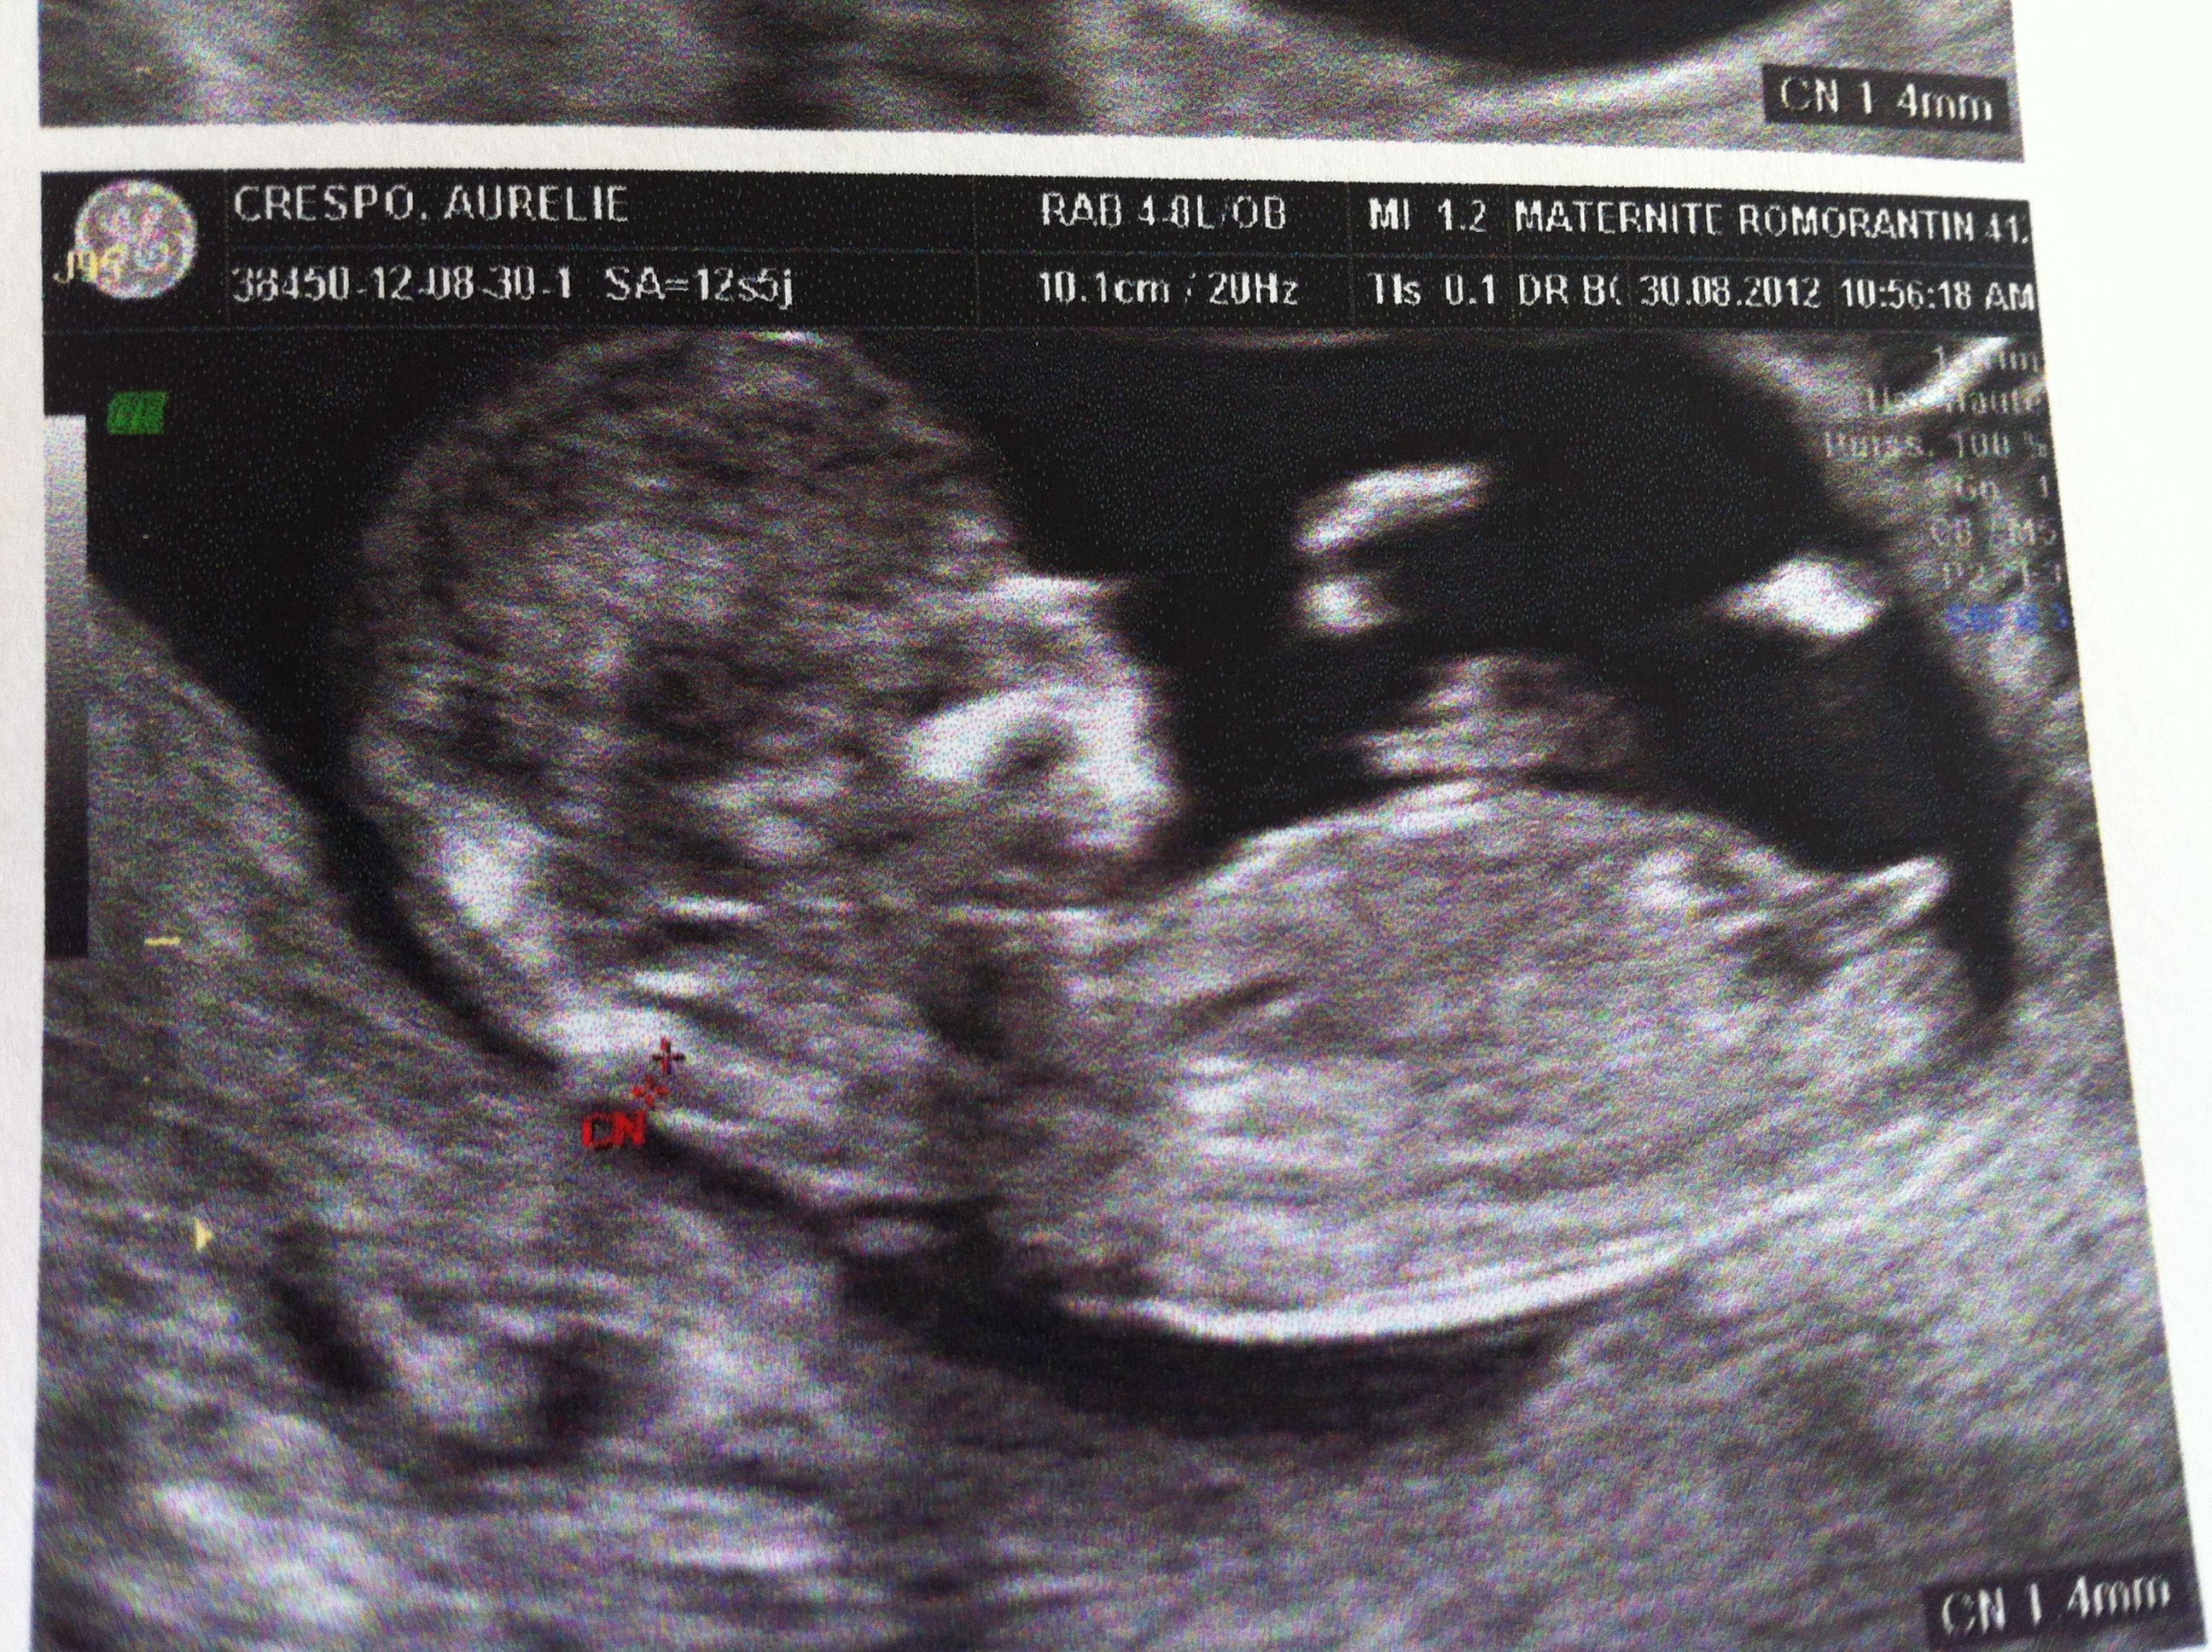

Estil possible de choisir le sexe de bébé?Echo Show 8 (1st Gen, 19 release) HD smart display with Alexa – Unlimited Cloud Photo Storage – Digital Photo Display Charcoal Amazon $ $ 109 99 (238,125)Ainsi dans de bonnes conditions techniques (échographiste entrainé, échographe performant et adapté à l'échographie de grossesse, bon passage des ultrasons à travers la paroi maternelle, bonnes positions du foetus et surout terme de grossesse supérieur à 12,5 SA), le diagnostic du sexe foetal est possible dans plus de 90 % des cas au premier trimestre

Analyser son échographie pour connaître le sexe de bébé Il vous faut donc passer l'échographie T1 (entre 11 et 13 semaines d'aménorrhée) pour avoir des éléments de réponse C'est généralement un grand moment dans votre calendrier de grossesse, émouvant pour les parents, car le fœtus commence à ressembler à un bébéLes envies peuvent également indiquer le sexe du bébé Quand on a envie de manger des produits sucrés, comme du chocolat, des biscuits, ou des bonbons, c'est une fille à l'intérieur du ventre Si l'on opte plutôt pour des frites ou n'importe quelle autre forme d'apéritif salé, c'est un garçonLa 1ère chose qu'elle nous a demandé, c'était de savoir si on voulait connaitre le sexe de cookie En France, il avait fallu qu'on demande au gynéco (un vieux monsieur un peu bourru) à la fin de l'examen pour savoir pour Mlle E lors de cette écho

Selon l'angle d'inclinaison du bourgeon, vous pouvez deviner le sexe de bébé Pour un garçon Le tubercule pointe vers le haut et forme un angle de plus de 30° avec la base de la colonne vertébrale Pour une fille Un angle entre le dos du foetus et le tubercule génital inférieur à 10° en faveur d'une petite filleNecesito sexo y estoy sola No aguantó más Hola Chicas al papa de mi bebé no lo veo desde que quede embarazada El no da por terminado la relación pero tampoco se aparece Lo amaba mucho y estaba enamorada Ahora decidí sólo hablar con el del bebé por que evidentemente el no tiene apuro por verme Me hubiese encantado compartir con el esta experienciaMoi je ne les pas su a la premiere echo la gyneco ma dit que cetait trop tot jetais deg car autour de moi on arretait pas de me dire que je saurais le sexe mais bon maaliche jai fait une echo 3d a 15semaine et cest la que je les su!!!!!!!!!!!!

Échographies Le moyen le plus fiable de connaître le sexe du bébé est l'échographie"La première échographie se déroule au cours du troisième mois de grossesse entre la 11e et la 13e semaines d'aménorrhéeDans certains cas, le sexe du bébé peutêtre annoncé lors de ce premier examen", explique le Dr Philippe Mironneau, gynécologue etCe matin, nous avons fait notre deuxième échographie Ce matin, après avoir un peu stressé parce que la sagefemme ne disait rien en regardant ce petit cœur battre, elle nous a rassuré en nous disant que tout allait bien pour ce beau bébé de 500 g, qui avait bien poussé Ce matin, nous avons appris qu'une petite fille viendraitRevelation du sexe de bebe , on attend c'est le grand jour, on connait enfin qui se cache dans mon ventreNous sommes des futurs parents comblé♡ Abonne to